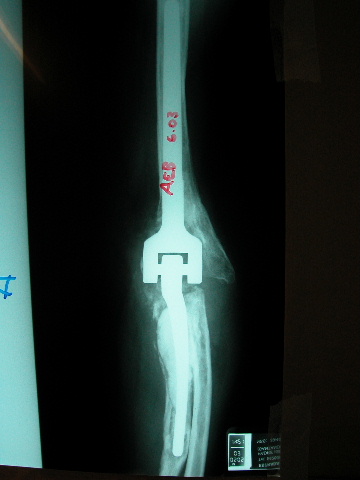

Prótesis completa de rodilla. Situación postquirúrgica.

Prótesis completa de rodilla. Situación postquirúrgica. Lateral.

Prótesis completa de rodilla.Lateral.

Prótesis completa de rodilla. Frontal.

Prótesis completa bilateral de rodillas.